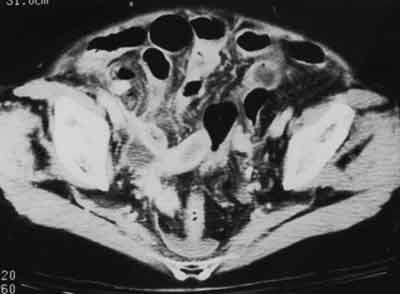

Abdominal pain in older patients is a medical Pandora’s box-some die, many need surgery, and the cause often remains unknown. An 84-year-old woman presented with nausea, vomiting, and constant lower abdominal pain. Abnormal urinalysis results and a normal WBC count were consistent with a urinary tract infection. This helical CT scan suggested perforating appendicitis. Surgical exploration revealed acute suppurative appendicitis with rupture.

Image courtesy of Carolyn J. Sachs, MD, MPH.